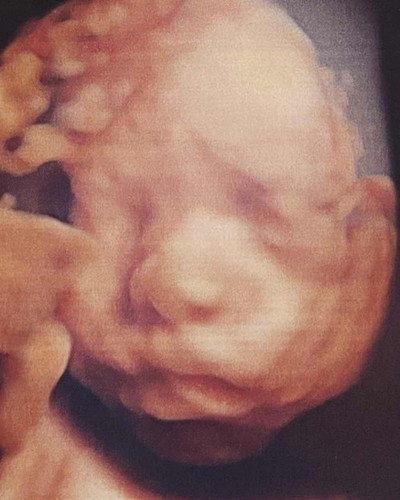

ภาพเพื่อนๆเป็นไงมั่งคับ 28week

ผมหล่อมั้ย❤️❤️28สัปดาห์แล้วคับ